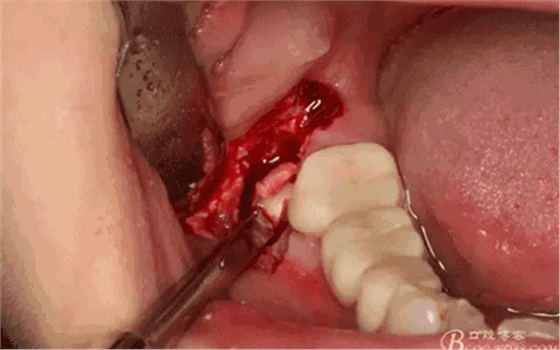

圖8.在頰側(cè)做角形切口